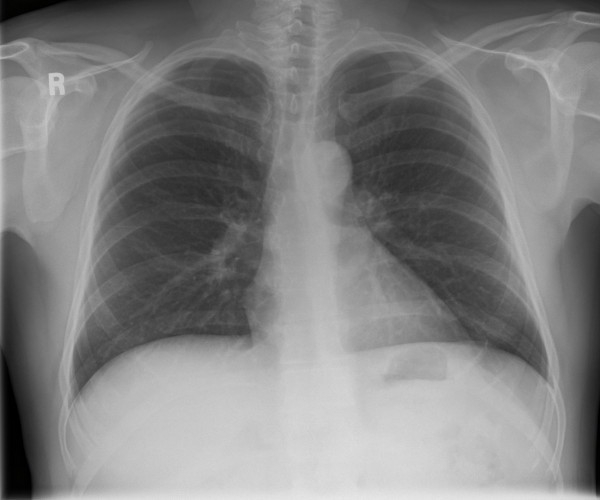

Thoracic Injuries: From Conventional X-Ray To Multidetector CT

Spectrum of lesions to be assessed in thoracic trauma Have great medical importance, social and (aortic injury) Multiple rib fractures (flail rib, CLASSIFICATION OF ... Fetch Document